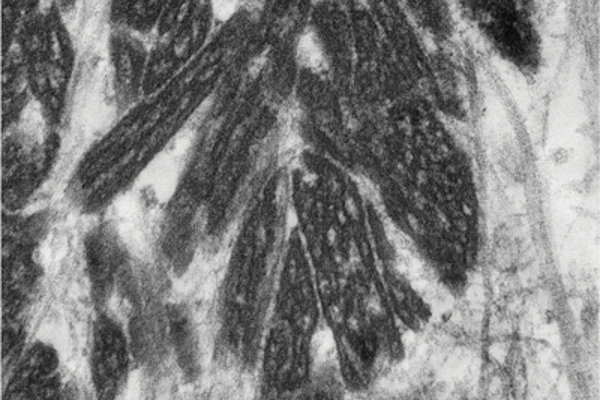

Pathology Quiz - Section Editor until Aug/Sep 2016